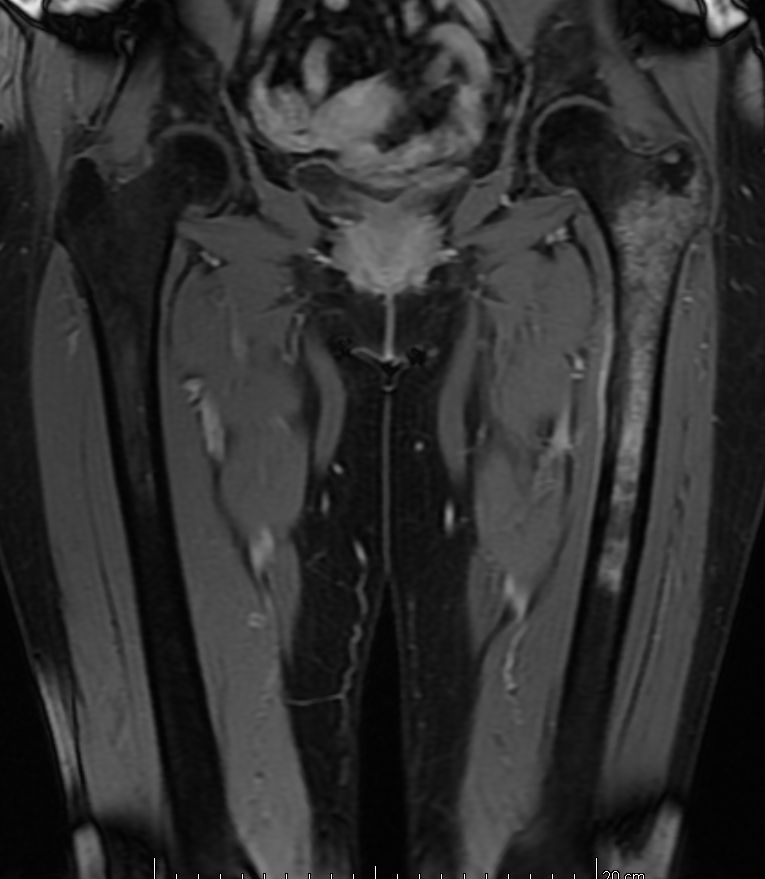

Femur | 58-jährige Frau mit Mammakarzinom links vor 14 Jahren und Mammakarzinom rechts vor 2 Jahren. Seit 4 Monaten Schmerzen im linken Oberschenkel. Jetzt Lungenmetastasen, osteoplastische Metastasen im LWk1 bis LWK4 sowie eine Osteolyse im linken Femur. | ||||||||||

MRT T2 KM Fett - saturiert![]() |

MRT T2 KM Fett - saturiert![]() | ||||||||||

MRT T1 KM Fett-saturiert![]() |

MRT T1 KM Fett-saturiert![]() | ||||||||||